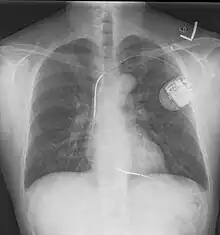

An implantable cardioverter-defibrillator (ICD) or automated implantable cardioverter defibrillator (AICD) is a device implantable inside the body, able to perform defibrillation, and depending on the type, cardioversion and pacing of the heart. The ICD is the first-line treatment and prophylactic therapy for patients at risk for sudden cardiac death due to ventricular fibrillation and ventricular tachycardia.[1]

The process of implantation of an ICD system is similar to implantation of an artificial pacemaker. In fact, ICDs are composed of an ICD generator and of wires. The first component or generator contains a computer chip or circuitry with RAM (memory), programmable software, a capacitor and a battery; this is implanted typically under the skin in the left upper chest. The second part of the system is an electrode wire or wires that, similar to pacemakers, are connected to the generator and passed through a vein to the right chambers of the heart. The lead usually lodges in the apex or septum of the right ventricle.[6]

Just like pacemakers, ICDs can have a single wire or lead in the heart (in the right ventricle, single chamber ICD), two leads (in the right atrium and right ventricle, dual chamber ICD) or three leads (biventricular ICD, one in the right atrium, one in the right ventricle and one on the outer wall of the left ventricle). The difference between pacemakers and ICDs is that pacemakers are also available as temporary units and are generally designed to correct slow heart rates, i.e. bradycardia, while ICDs are often permanent safeguards against sudden life-threatening arrhythmias.

Initially ICDs were implanted via thoracotomy with defibrillator patches applied to the epicardium or pericardium. The device was attached via subcutaneous and transvenous leads to the device contained in a subcutaneous abdominal wall pocket. The device itself acts as an electrode. Most ICDs nowadays are implanted transvenously with the devices placed in the left pectoral region similar to pacemakers. Intravascular spring or coil electrodes are used to defibrillate. The devices have become smaller and less invasive as the technology advances. Current ICDs weigh only 70 grams and are about 12.9 mm thick.